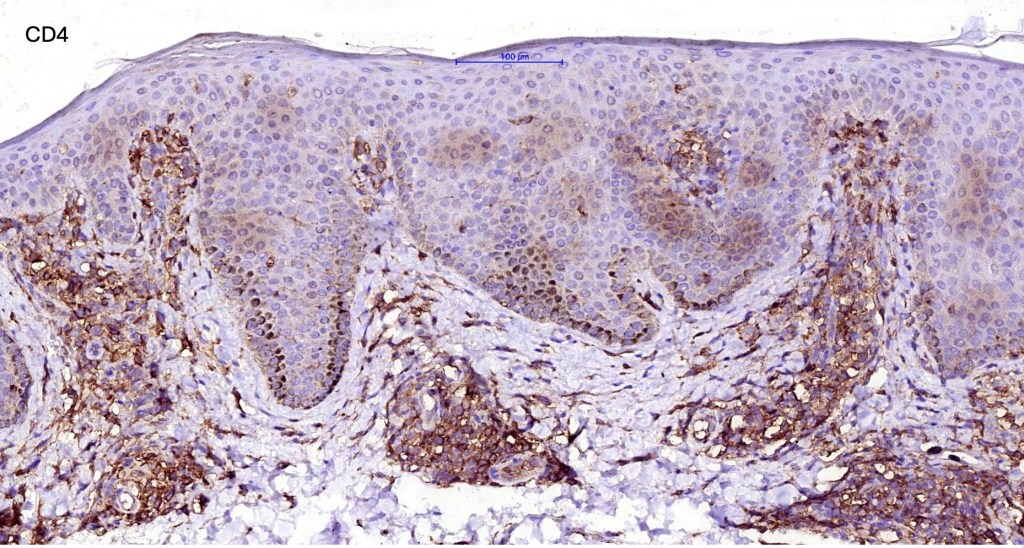

•Sézary cells are CD45RO, CLA, CD158 & CD4+

.Loss of CD7 (40% or more) & CD26 (30% or more)